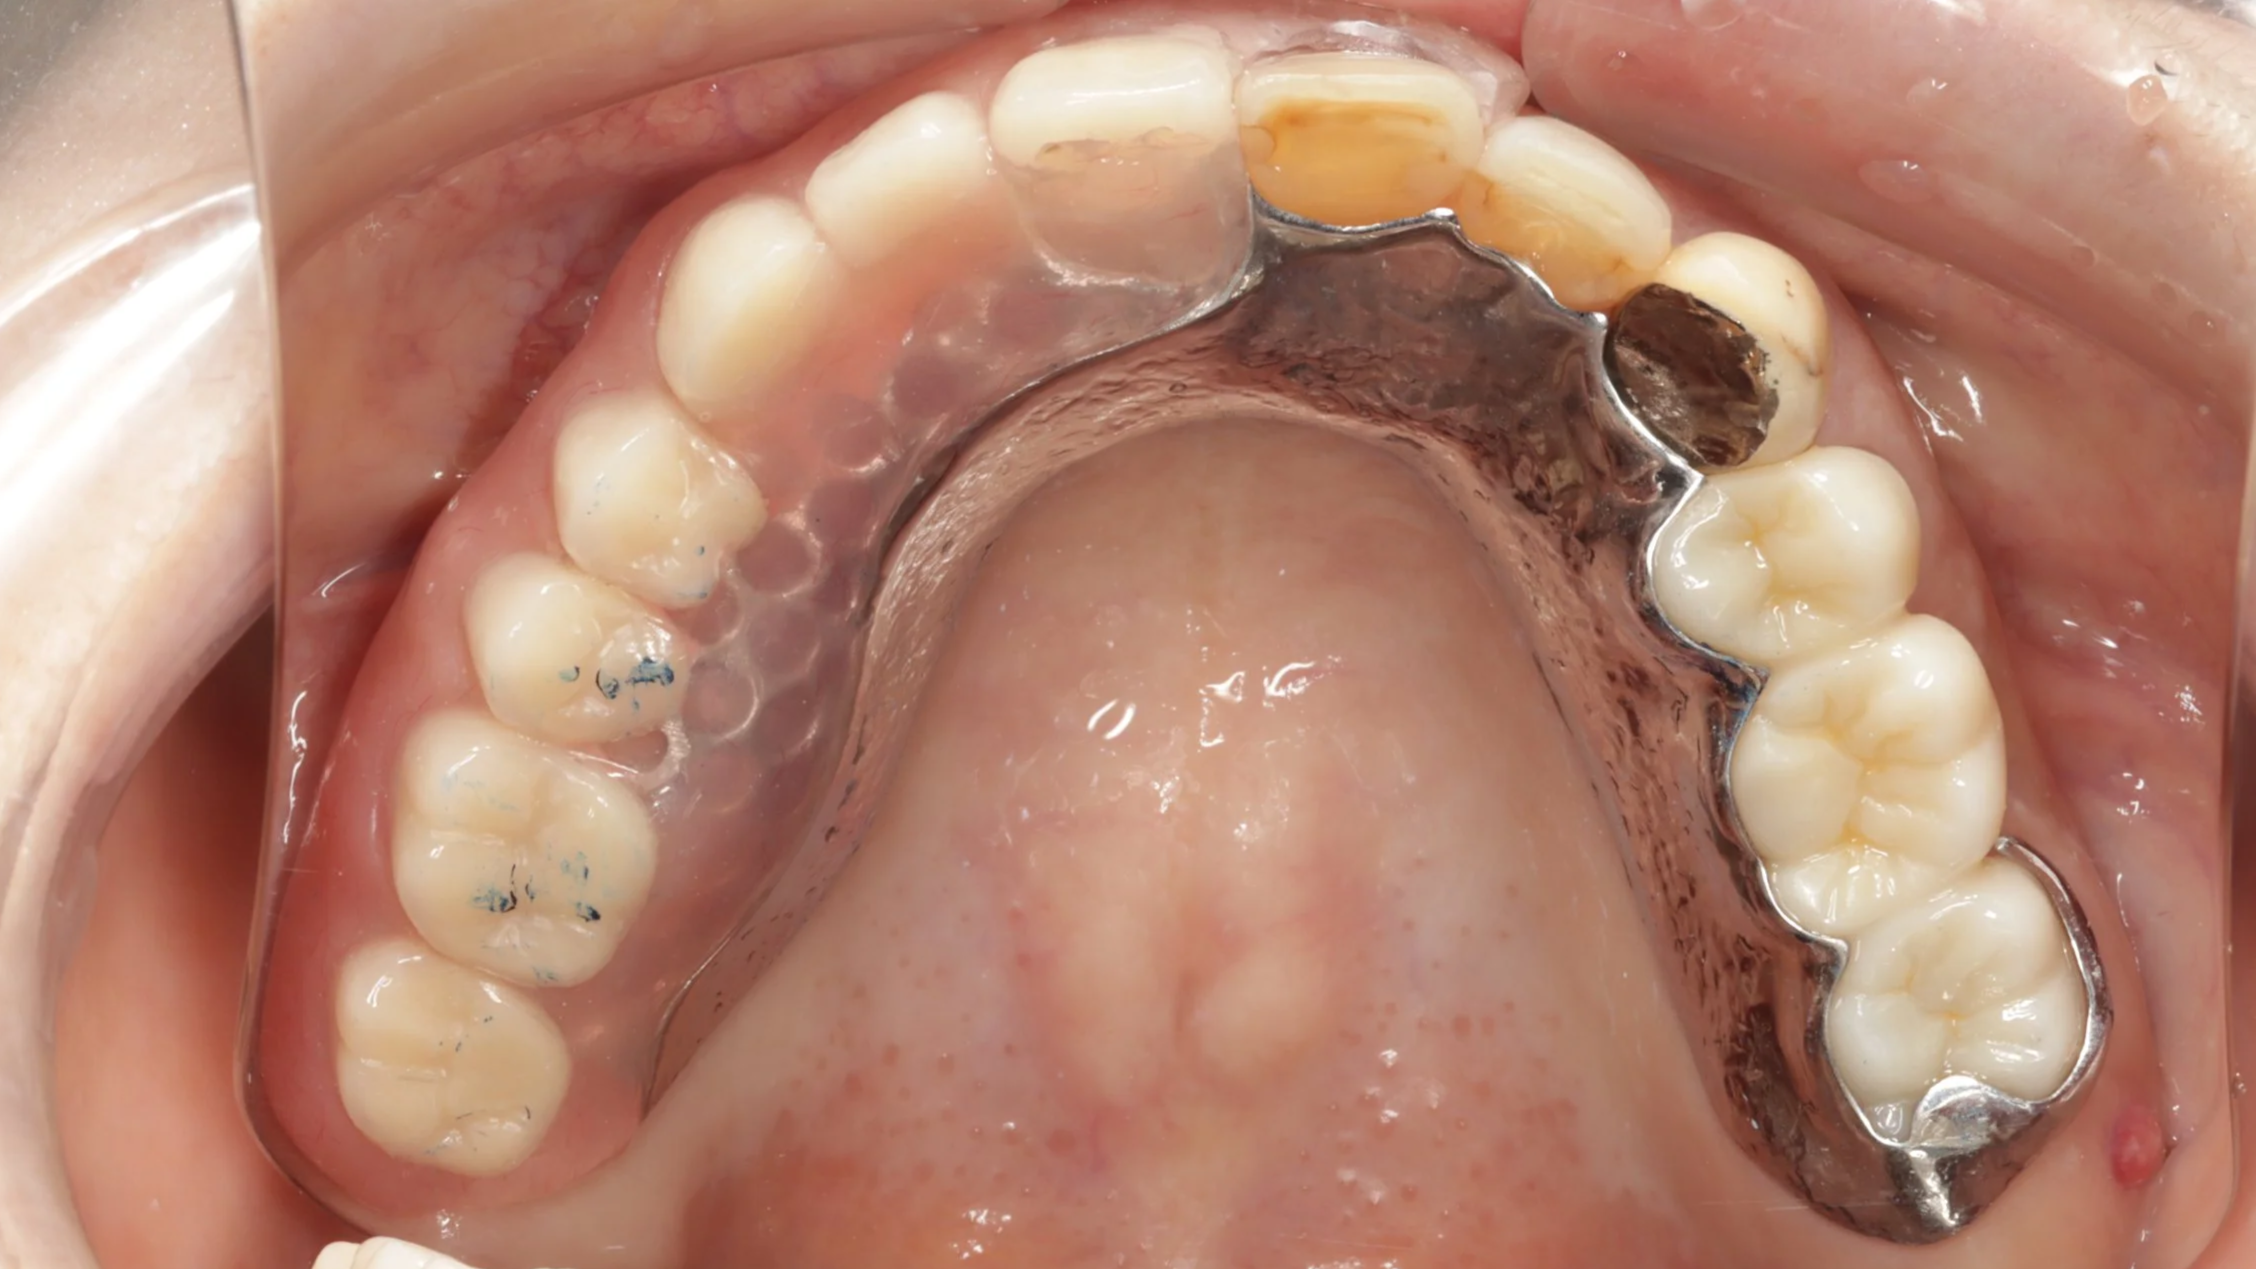

2回目

今回はできるだけ薄く作りたいという希望もあったことから、金属床を用い製作、前歯の抜歯とともに同日に新しい入れ歯を装着。

デジタルデンチャー

奥の歯には、金属で入れ歯を止めるバネを製作し、前歯の見える部分には、透明なレジンクラスプを使用しました。